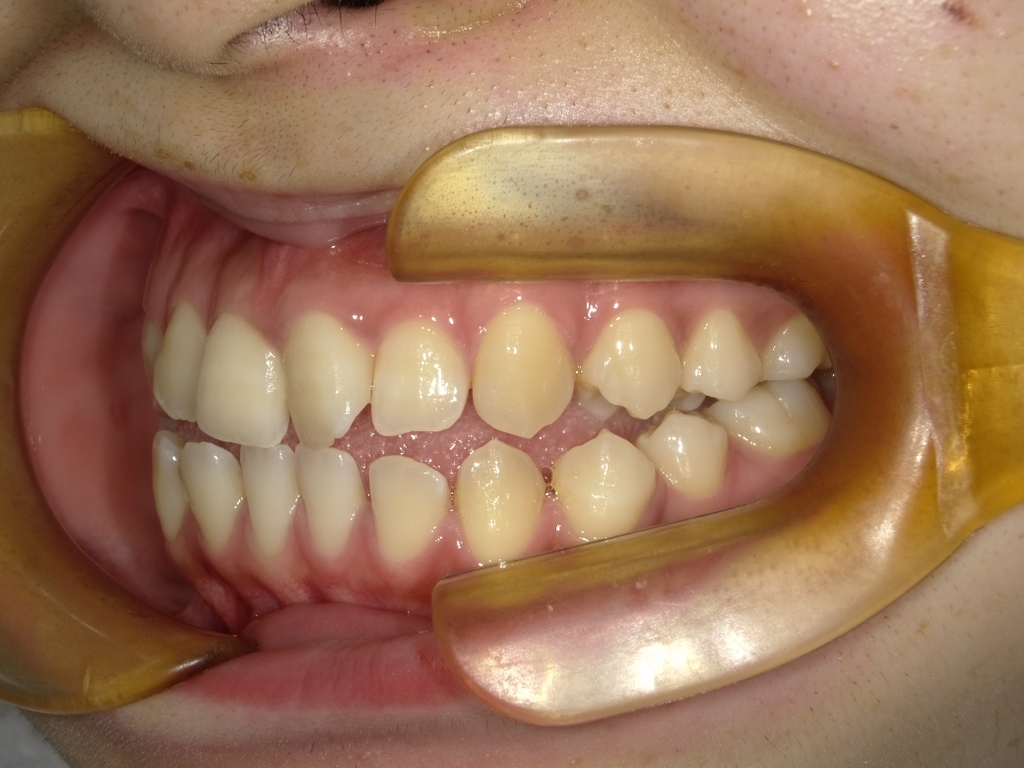

治療前